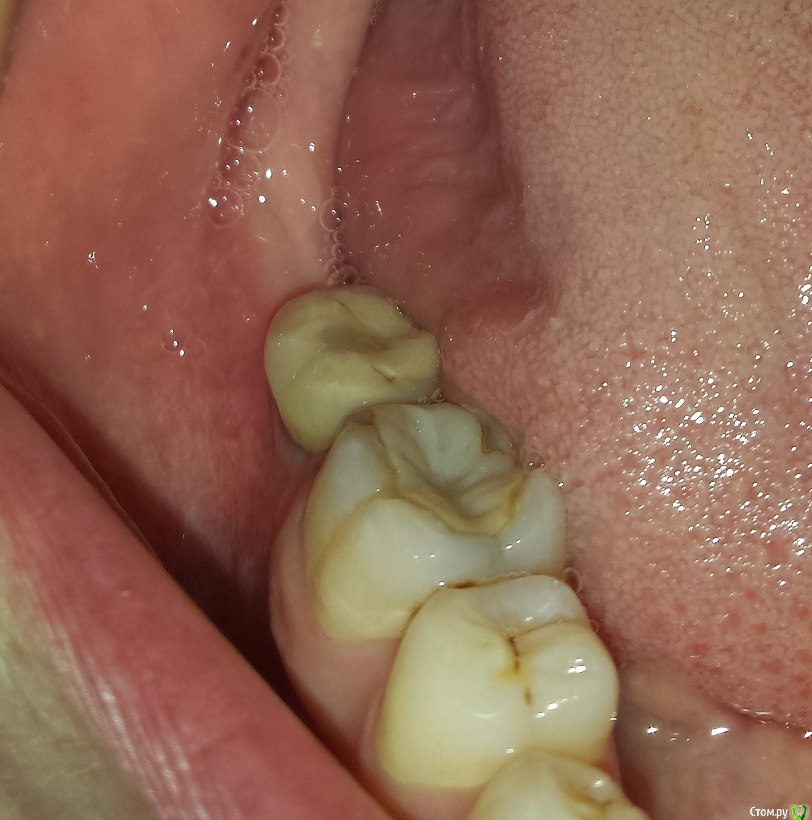

permico Опубликовано 23 августа, 2017 Поделиться Опубликовано 23 августа, 2017 (изменено) Добрый день.Примерно год назад во Франции мне были установлены 2 импланта на нижнюю челюсть взамен отсутствующих семерок (восьмерки были удалены еще раньше), т.е.37 и 47 зубов. Система Implant Direct (США), тип Swish plus, длина 10 мм. диаметр 5.7 и 4.1 мм. Врач уверил, что они являются репликой трансгингивальных Straumann Tissue Level с полированной шейкой и полностью совместимы. В общем, интегрировались они нормально, коронки он установил и я с ними проходил год без жалоб.Недавно сходил здесь в Москве к стоматологу, чтоб подкрутить винты на имплантах. Он все сделал и сказал, что нужно мне показаться хирургу-имплантологу так как они установлены скорее всего неправильно, забивается много пищи между коронками и десной (они сделаны с "балконом") и очень вероятно осложение в виде резорбции костной ткани. Сходил на консультацию к одному хирургу в Москве, он сказал, да действительно они неправильно установлены и им поможет только вынимайзинг с последующей установкой новых на то же место. Если сейчас не переустановлю, то через примерно пять лет их в любом случае придется вынимать, так как винт начнется оголяться, но уже кости будет меньше и будет труднее устанавливать новые.Хотел бы совета от специалистов на форуме, действительно ли они требуют удаления или можно сделать что-то другое. чтобы решить проблему.Прикладываю изображения (панорамный снимок после операции, недавние снимки имплантов, и фото их во рту, последние не очень хорошего качества, вечером могу попробовать переснять)Спасибо заранее, Борис Изменено 23 августа, 2017 пользователем permico Ссылка на комментарий

Art 7 Опубликовано 23 августа, 2017 Поделиться Опубликовано 23 августа, 2017 если хотите продлить жизнь имплантатам то надо выкрутить коронки, сделать пластику десны вокруг имплантатов и переделать коронки. это даст много лет жизни ималантатам 5 Ссылка на комментарий

brg Опубликовано 23 августа, 2017 Поделиться Опубликовано 23 августа, 2017 36, 46 нужно лечить. Ссылка на комментарий

Zlata-doctor Опубликовано 24 августа, 2017 Поделиться Опубликовано 24 августа, 2017 соседние с имплантами зубы нуждаются в лечении Ссылка на комментарий